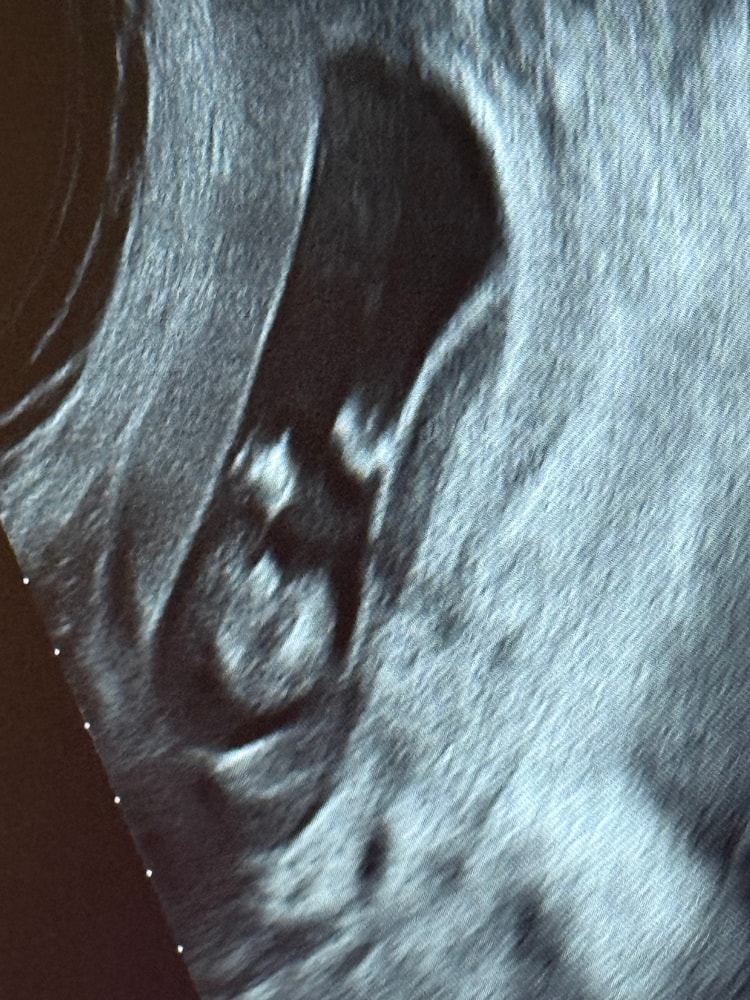

Похоже ли на член?😅

99% это мальчик. На фото не писюн а яички )

Ну если я правильно поняла фото, и это вид снизу между ног, то скорее похоже на мальчика. Но сказать точно, этот "торчок" член или часть пуповины - невозможно. Потому, это только гадать. Мне в 15 недель при более чётком фото дали только 80% на девочку. В 20 недель подтвердили.

Анастасия, ну вот я помню как выглядел член, и он был ровно между ног, а тут как-то криво и плюс да, между ног была пуповина🫠